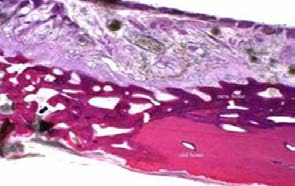

Paraffin section of mouse spine showing metastatic breast cancer, decaled section H&E Stain